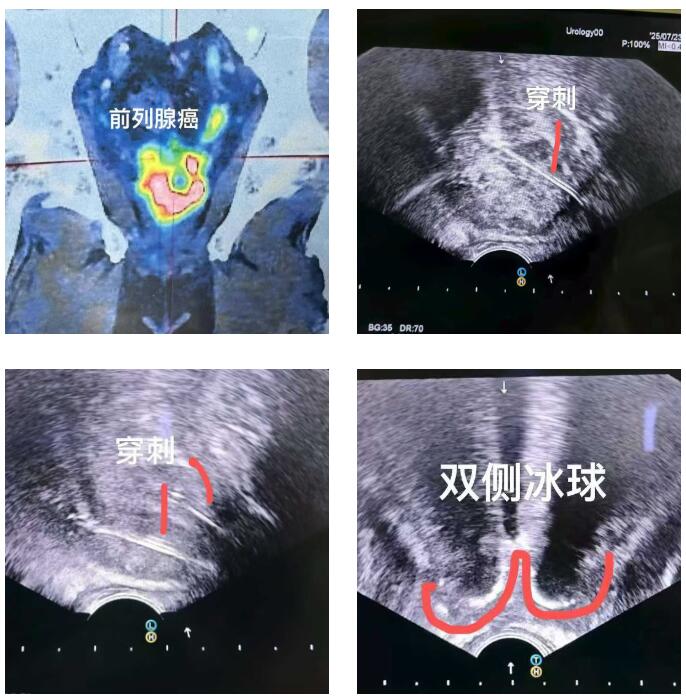

比如这位马来西亚患者,PSA指标正常,但影像却发现可疑病灶,结果穿刺证实是少见的前列腺尿路上皮癌,在我院接受了冷冻消融治疗。